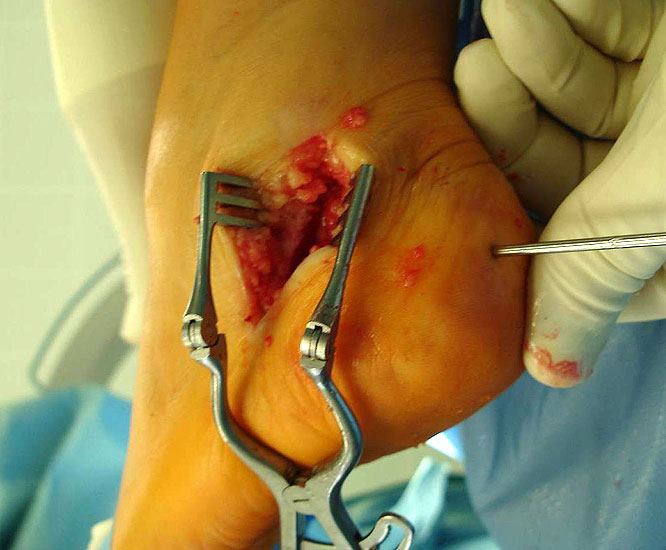

715.<br> Für die medialisierende Calcaneusosteotomie wird ein bogenförmiger Hautschnitt in Höhe des hinteren Fersenbeines gesetzt, die Subcutis bis zum Fersenbein durchtrennt und dieser bogenförmige Lappen nach ventral präpariert. Dadurch kommt es zu einem Schutz des Nervus suralis, welcher gemeinsam mit den Peronealsehnen nach vorne gehalten wird.<br> Es wird nun das Fersenbein mit einem Wundspreizer eingestellt und cranial sowie caudal mit 2 Hohmannhaken umfahren.<br> Dann wird das Fersenbein mit der oszillierenden Säge osteotomiert, mit dem Meißel und dem Wundspreizer distrahiert.<br> Danach wird das Fersenbein ca. 1 cm nach medial verschoben, unter Vermeidung der Cranialisierung des hinteren Calcaneus . Dann wird von dorsal über eine Hautstichincision der Bohrdraht für die 4,5mm (- 6,5 mm) kanülierte Schraube eingebracht und über die Osteotomie in den vorderen Calcaneusanteil vorgeschoben.<br> Kontrolle im Bildwandler in 2 Ebenen. Wenn die Bohrdrahtlage gut ist Überbohren für die kanülierten Schrauben und Eindrehen der Schraube. (Alternativ kann an Stelle der Schraubentechnik auch eine Fixation mit Stufenplatten oder Ähnlichem verwendet werden).<br> Wundverschluss am lateralen Zugang und über der Stichincision.</p>"> 715.<br> Für die medialisierende Calcaneusosteotomie wird ein bogenförmiger Hautschnitt in Höhe des hinteren Fersenbeines gesetzt, die Subcutis bis zum Fersenbein durchtrennt und dieser bogenförmige Lappen nach ventral präpariert. Dadurch kommt es zu einem Schutz des Nervus suralis, welcher gemeinsam mit den Peronealsehnen nach vorne gehalten wird.<br> Es wird nun das Fersenbein mit einem Wundspreizer eingestellt und cranial sowie caudal mit 2 Hohmannhaken umfahren.<br> Dann wird das Fersenbein mit der oszillierenden Säge osteotomiert, mit dem Meißel und dem Wundspreizer distrahiert.<br> Danach wird das Fersenbein ca. 1 cm nach medial verschoben, unter Vermeidung der Cranialisierung des hinteren Calcaneus . Dann wird von dorsal über eine Hautstichincision der Bohrdraht für die 4,5mm (- 6,5 mm) kanülierte Schraube eingebracht und über die Osteotomie in den vorderen Calcaneusanteil vorgeschoben.<br> Kontrolle im Bildwandler in 2 Ebenen. Wenn die Bohrdrahtlage gut ist Überbohren für die kanülierten Schrauben und Eindrehen der Schraube. (Alternativ kann an Stelle der Schraubentechnik auch eine Fixation mit Stufenplatten oder Ähnlichem verwendet werden).<br> Wundverschluss am lateralen Zugang und über der Stichincision.</p>" srcset="/assets/images/a/3-raswd6qgkh6s353.jpg 1x, /assets/images/g/3-exngvjjv83x827d.jpg 1.5x, /assets/images/w/3-836r57qt8j3eh0w.jpg 2x" width="270" height="240" loading="lazy">

Abbildung 4

8. Bei Bedarf kann zur Verstärkung des talonavicularen Kapsel-Bandapparates der Stumpf der Tibialis posterior Sehne verwendet werden</p>"> 8. Bei Bedarf kann zur Verstärkung des talonavicularen Kapsel-Bandapparates der Stumpf der Tibialis posterior Sehne verwendet werden</p>" srcset="/assets/images/4/5-b32ybaf1nq8e0pj.jpg 1x, /assets/images/9/5-djkrnnkb21s2gpr.jpg 1.5x, /assets/images/5/5-gmxasnncbyn5dbb.jpg 2x" width="270" height="240" loading="lazy">

Abbildung 5